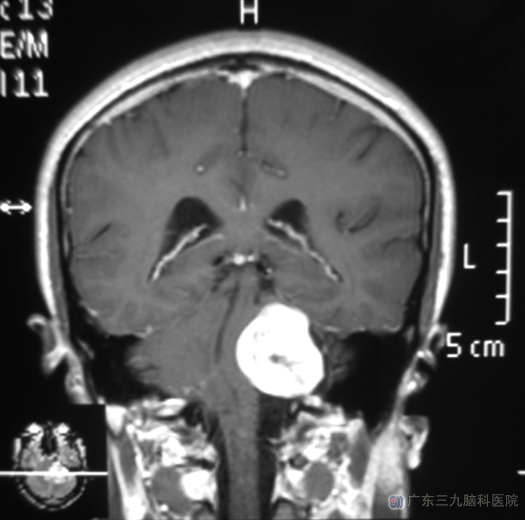

一直到出现头晕,特别是走路时明显后,才做了头颅CT检查,提示:左侧桥小脑角占位。广东三九脑科医院综合神经外科 鲁明主任查体发现:黄先生左侧角膜反射消失,左侧面部感觉消退,闭目难立征、指鼻试验阳性。经头颅MR检查提示肿瘤大小约3.8cm×3.4cm×3.0cm。

▲手术前